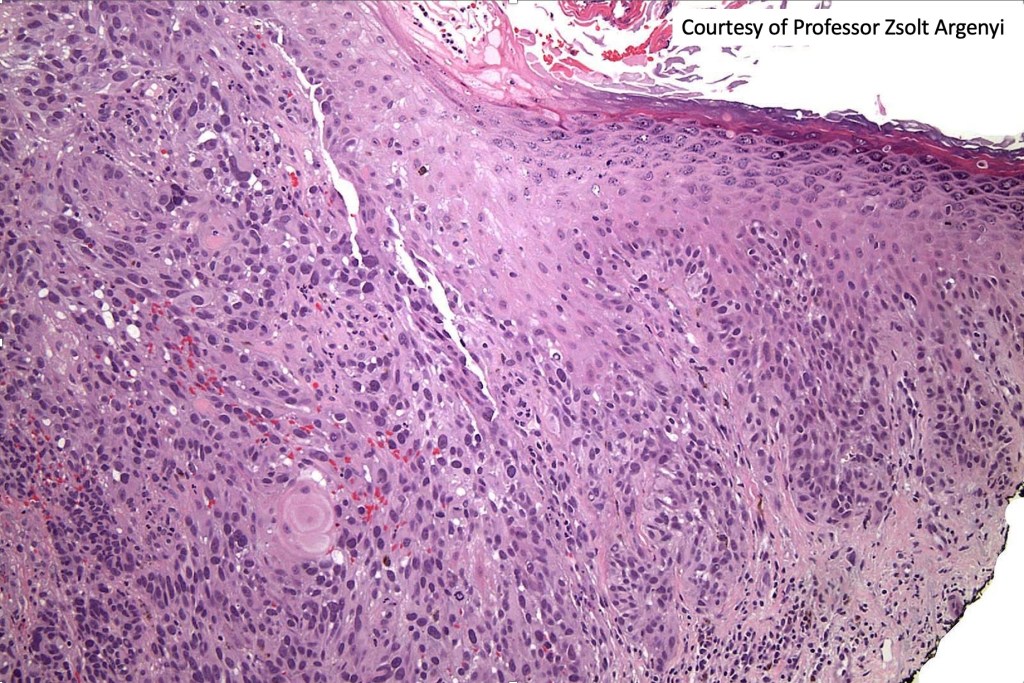

Clear cells may be intermingled with balloon cells in balloon cell melanoma. Only very exceptionally is a melanoma be composed of an almost pure cell population- clear cell melanoma. The clear cells differ from balloon cells in that they contain excessive amounts of glycogen which can be confirmed with a PAS stain. Clear cell melanoma must be distinguished from primary cutaneous or metastatic clear cell sarcoma and other clear cell tumors/carcinomas. Clear cell melanoma will likely show a junctional component in primary tumors, melanin pigment and positivity for S100 & HMB45. Clear cell sarcoma shows a characteristic t(12;22)(q13-14;q12 translocation, not present in melanoma.